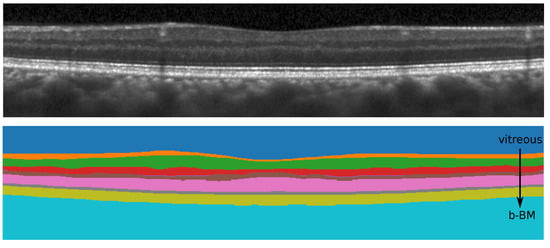

Our segmentation method consists of two cascaded U-Net-like architectures, as shown in Figure 1. The first network, termed RS-Net (retinal segmentation network), is responsible for segmentation of the retina from a full OCT B-scan. In its simplest form, this is the retinal tissue between the inner limiting membrane (ILM) and Bruch’s membrane (BM) as boundaries. The trained network takes a preprocessed OCT B-scan as input and produces a three-class output: purple region (above ILM), green region (retinal region) and yellow region (below BM) (Figure 1). The output of RS-Net and the original input serve as the input for the second network. The second network, the intraretinal layer segmentation network (IS-Net), takes the two-channel input and generates a 9-class output providing boundaries for 8 different intraretinal layers and membranes: ILM—inner limiting membrane, mRNFL—macular retinal nerve fiber layer, GCL—ganglion cell layer, IPL—inner plexiform layer, GCIPL—macular ganglion cell/inner plexiform layer, INL—inner nuclear layer, OPL—outer plexiform layer, ONL—outer nuclear layer, ELM—external limiting membrane, MZ—myoid zone, EZ—ellipsoid zone, OS—outer segment, RPE—retinal pigment epithelium, OL—outer layer and BM—Bruch’s membrane (Figure 2).

DSC values were computed between manually corrected segmentation using the SAMIRIX toolbox and the proposed method’s outcome for nine classes for CUB and UCLA. The corresponding values are reported in Table 6, where vitreous is the region above ILM and b-BM is the region below BM, as shown in Figure 7. As can be seen from Table 6, the first and the last classes (vitreous, b-BM) yield the highest DSC values (close to 1) as the differences between the numbers of background and foreground pixels are small. Moreover, OPL has the lowest value of DSC since this is one of the thinnest layers and the difference between the numbers of background and foreground pixels can be large. Compared to the state-of-the-art methods, our method produces better overall DSC scores (CUB-0.95, UCLA-0.94 and JHU-0.92), except [38,48], where validations are performed using HC data only.

Figure 1. The pipeline of the proposed method consists of four steps: preprocessing, retinal region segmentation, intraretinal layer segmentation, and postprocessing.

Figure 7. All nine different classes segmented by the proposed method.